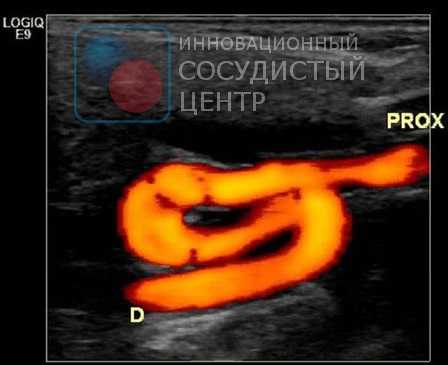

Начальная диагностика для выявления поражения позвоночной артерии на шее проводится с помощью УЗИ с цветовым допплеровским картированием. Ультразвуковое исследование позволяет выявить патологию сосудов у большинства пациентов, однако этот метод зависит от используемой аппаратуры и навыков врача УЗИ. Метод позволяет выявить сужение в шейном отделе позвоночной артерии, структуру атеросклеротической бляшки, характер кровотока по позвоночной артерии. Транскраниальная допплерография (ТКД) применяется для обнаружения внутричерепного стеноза позвоночной артерии. Метод позволяет в 80% случаев выявить нарушение кровотока в базилярной и позвоночных артериях, возможно исследование с детекцией эмболии (переноса кусочков бляшки в мозговые сосуды), что доказывает роль сужения в развитии нарушений мозгового кровообращения.

УЗИ сонных и позвоночных артерий

Ультразвуковое сканирование сонных артерий является безопасным и информативным методом диагностики многих заболеваний этих сосудов. У пациентов старше 55 лет это исследование необходимо выполнять ежегодно, для выявления факторов риска ишемического инсульта.

УЗИ магистральных артерий головы — неинвазивный метод визуализации, который посредством регистрации отражённых ультразвуковых волн позволяет получить информацию об индивидуальных анатомических особенностях, протяжённости и степени поражения артерий, а также оценить влияние этих факторов на кровоток.

Исследование абсолютно безболезненно и не доставляет пациенту существенного дискомфорта. Высокая диагностическая ценность исследования связана с тем, что специалист в режиме реального времени получает представление об анатомических образованиях и характере кровотока в сонных артериях.

Ультразвуковое исследование сонных и позвоночных артерий (УЗИ МАГ) проводится для выявления факторов риска ишемического инсульта. Сегодня уже доказано, что атеросклеротическое сужение внутренних сонных артерий значительно увеличивают риск инсульта из-за тромбозов сонной артерии или эмболии - переноса кусочка бляшки в мозговые сосуды. Это утверждение справедливо и для позвоночных артерий.